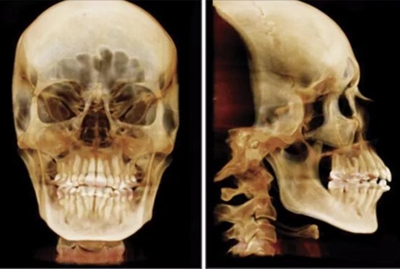

患者曾行正畸治療,現(xiàn)覺(jué)笑容不美觀前來(lái)就診。患者正面觀及側(cè)貌示下頜發(fā)育不足,偏高角,唇閉合不全。上下頜中線齊。覆合、覆蓋4毫米。磨牙關(guān)系及尖牙關(guān)系II類(lèi)。上頜擁擠度4mm,下頜擁擠度6mm。4顆第一前磨牙在第一次正畸治療時(shí)已拔除。上下牙弓呈尖圓型,牙弓狹窄。

頭影測(cè)量分析,SNA角84°,ANB角6°,高角型,詳見(jiàn)下表。

患者側(cè)貌改善,下唇唇肌緊張消失,上下唇可自然閉合。磨牙及尖牙關(guān)系糾正至I類(lèi),覆合覆蓋正常。上下頜弓型糾正至卵圓形,牙弓寬度增加。頭影測(cè)量分析示SNA角81.8°,ANB角3°。頭影測(cè)量重疊圖示下頜骨向后旋轉(zhuǎn),垂直面高度略有增加。